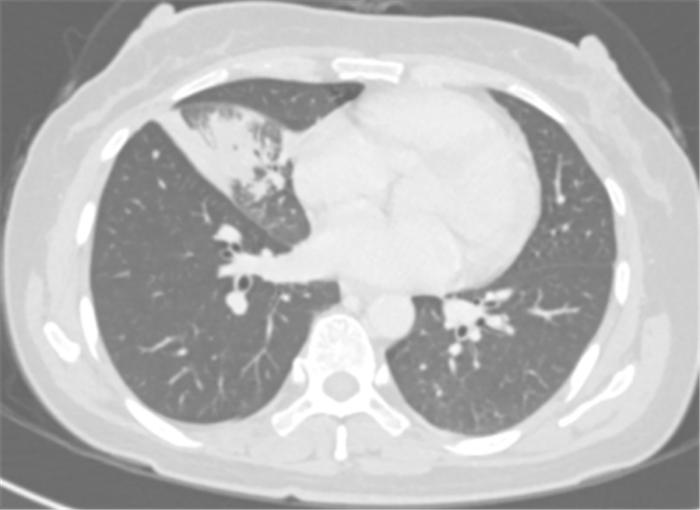

经过4个周期的治疗后复查发现:李女士的病灶明显缩小,实现了降低肺癌分期。

免疫联合化疗新辅助治疗4周期后胸部CT